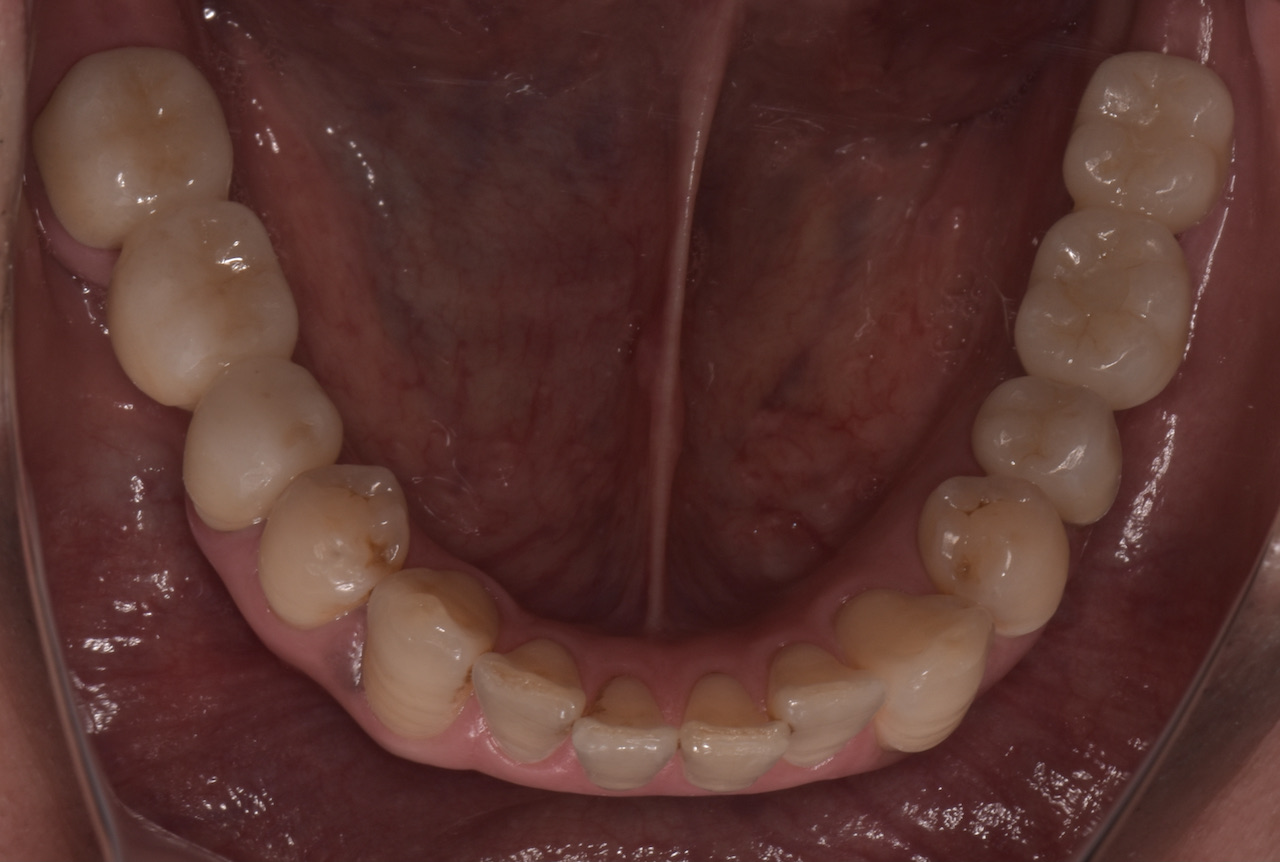

この患者さんは50代の男性で、若い時から様々な歯科治療をなさり、それに伴って抜歯をされたり、咬めなくなったそうです。そのなかで徐々に咬む位置がが分からなくなってきたとい言うお悩みで名取歯科医院にご来院されました。 全顎的に複数の治療部位で、インプラント・ブリッジ・ダイレクトボンディング・セラミッククラウンなど、適切な治療方法を組み合わせて包括的な治療を終え顎関節症の改善と咬めないという永きにわたるお悩みを解消しました。

顎関節の精密検査を行うと顎の状態も左右で異なり、咬み合わせもズレが大きくなったことで歯が欠けるなど、不調の理由がわかりました。

顎関節の軟骨(関節円板)がずれ、それに伴って咬み合わせが変化しても当時の歯科医師が適切な咬み合わせ(咬合調整)しなかったため、そのストレスが長年にわたり顎関節に影響し、痛みを生じてきたと検査から考えられました。

精密検査の中で「T-scan」という咬み合わせの専用の機械を使って診断すると、奥歯以外ではしっかり咬む箇所がなく、明らかに咬み合わせのバランスが良くありません。

全顎的に複数の治療部位で、インプラント・ブリッジ・ダイレクトボンディング・セラミッククラウンなど、適切な治療方法を組み合わせて包括的な治療を進めました。

治療後